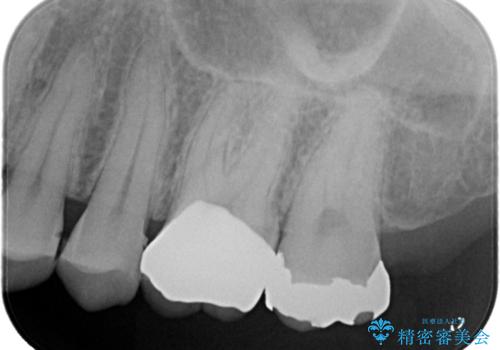

左上6の近心にカリエスを認め、残存歯質と破折リスクの観点からセラミッククラウンでのやり替えとなりました。

今後ホワイトニング行う予定のため、シェード明るめにしています。